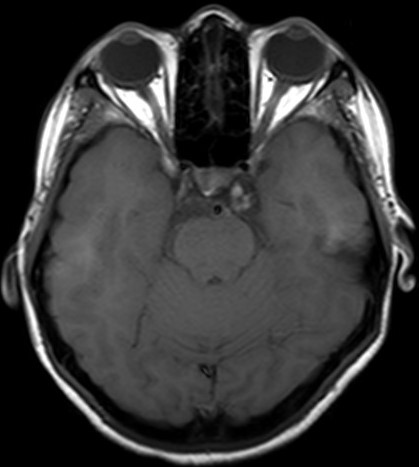

A hemangioma is a benign vascular tumor of the brain, which rarely occurs in the cavernous sinus. We report a rare case of cavernous sinus hemangioma presenting with binocular diplopia. A 23-year-old lady presented with binocular diplopia associated with restricted left lateral gaze for 3 months. Visual acuity of both eyes was 6/6 with normal pupillary reaction. Both anterior and posterior segment were unremarkable. Contrasted computed tomography of brain showed an irregular mass within the left cavernous sinus causing pressure effect on the adjacent bone. Cerebral magnetic resonance imaging (MRI) showed a convexity in the left cavernous sinus, with a well-defined heterogeneous lesion with mixed hypo and hyperintensity in T1WI and T2WI; post gadolinium contrast, it was minimally enhanced. The patient was managed conservatively and at one-year post presentation, her symptoms improved but the lesion morphology and size remained static. We highlight the classic radiological presentation of a hemangioma and discuss the features differentiating it from the more commonly observed meningioma seen in the cavernous sinus.References